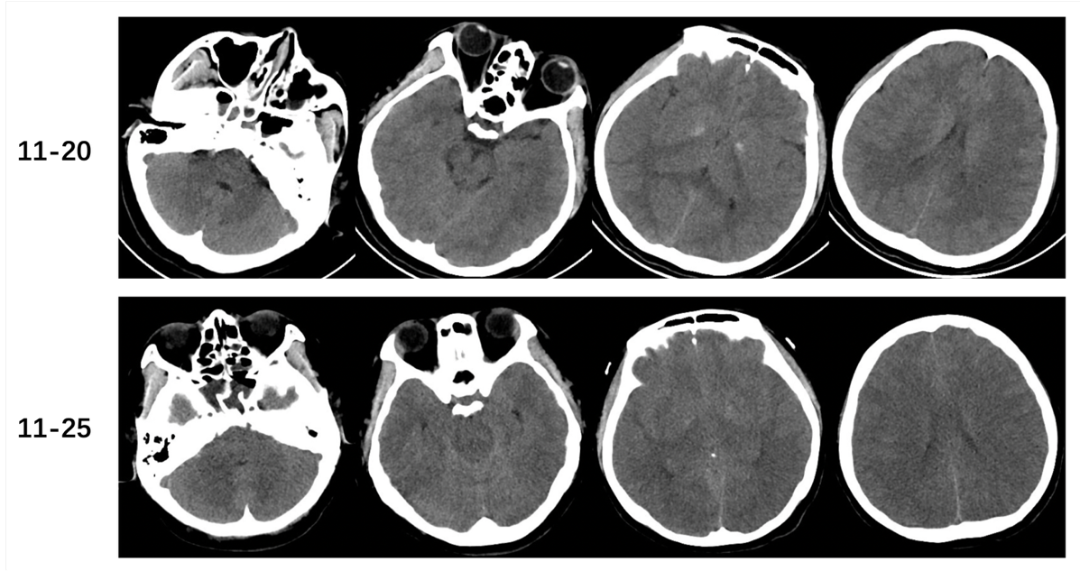

头颅CT:脑组织肿胀加重,部分脑沟裂池变浅、消失,丘脑可疑低密度影(2025年11月25日,图1)。

图1 头颅CT示脑组织肿胀(2025年11月20日);头颅CT示脑组织肿胀加重,部分脑沟裂池变浅、消失,丘脑可疑低密度影(2025年11月25日)。